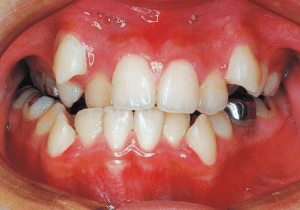

11 During observation 4-1-’93 Midline deviation has become even greater 11 years 9 month

X-rays confirmed significant differences in the length and orientation of the mandibular ramus on the left and right sides. It was determined that orthodontic treatment alone would be insufficient, and a decision was made to proceed with treatment incorporating surgical intervention.

Although early treatment improved the slight deviation observed during the deciduous dentition stage, it became apparent that the deviation increased with age, eventually exceeding the limits of treatment. This appears to be an innate deviation, and the developmental pattern observed in this case seems to disregard the occlusion. Four first premolars were extracted (15), crowding was corrected and space closure was performed (16), and surgical intervention improved the deviation (17).